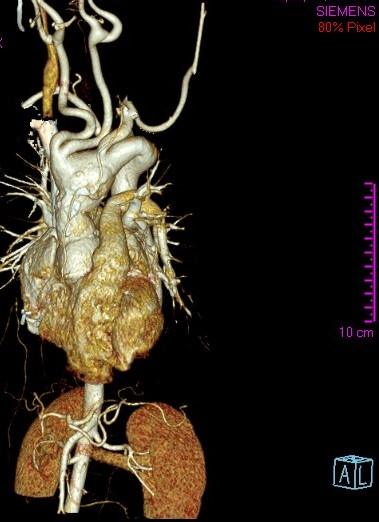

Figure 2. Three-dimensional CT reconstruction showing aneurysmal dilatation of the aortic root, ascending aorta, and aortic arch, tortuosity of supraaortic vessels, and aberrant right subclavian artery.

A 14-year-old female patient with clinical features of Loeys-Dietz syndrome presented to the authors’ institution with new onset atypical chest pain. The patient related a prior surgical correction of an ascending aorta aneurysm at 18 months of age, in addition to a sibling who had an ascending aorta aneurysm surgically corrected in early childhood. Transthoracic echocardiography showed a tricuspid aortic valve with mild insufficiency, dilation of the aortic root, and dilation at proximal and distal anastomosis of the ascending aorta Dacron tube, without stenosis. Supraaortic vessels showed a tortuous and dilated origin. Given the technical difficulty for surgical correction, computed tomography (CT) angiography of the thoracic aorta was requested with 3D reconstruction for surgery planning. This demonstrated postsurgical inflammatory changes, supraaortic vessels only 2 mm from the sternum, aneurysmal dilatation of the aortic root, ascending aorta, and aortic arch, tortuosity and dilatation of supraaortic vessels, aberrant right subclavian artery, and a normal descending aorta (Figures 1 and 2). A surgical plan was established and was followed throughout the operation by the entire team: